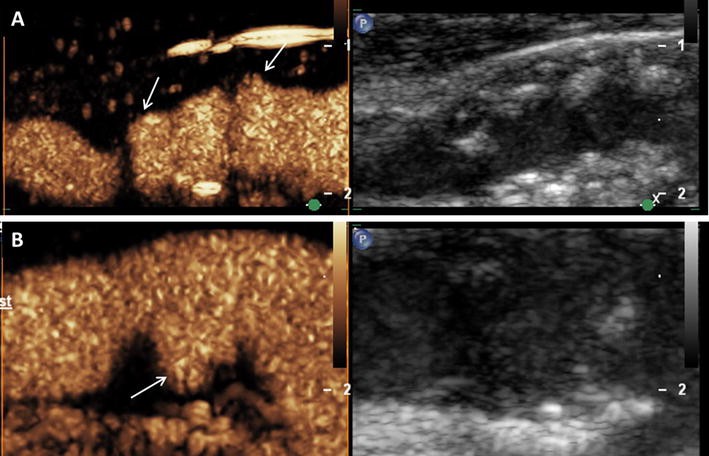

Assessment of vessel wall irregularities and plaque ulcerations on carotid artery using CEUS. a Mixed hypo- and hyperechoic plaques at the carotid bulb on B-mode ultrasound (right side) and CEUS imaging (left side) with surface irregularities (arrows). b Plaque ulceration (arrow) on CEUS imaging (left side) at the origin of the internal carotid artery not detected on B-mode ultrasound (right side)

Visual based grading of intraplaque neovascularization on CEUS imaging. a No enhancement: Small plaque on the fare wall of the internal carotid artery on B-mode ultrasound (right side) without intraplaque neovascularization on CEUS imaging (left side). b Moderate enhancement: Mixed hypo- and hyperechoic plaques at the carotid bulb on B-mode ultrasound (right side) and CEUS imaging (left side) with moderate intraplaque neovascularization on the plaque shoulder (arrows). c Extensive enhancement: Hypoechoic plaque at the origin of the internal carotid artery on B-mode ultrasound (right side) and CEUS imaging (left side) with extensive intraplaque neovascularization including the plaque core (arrows)